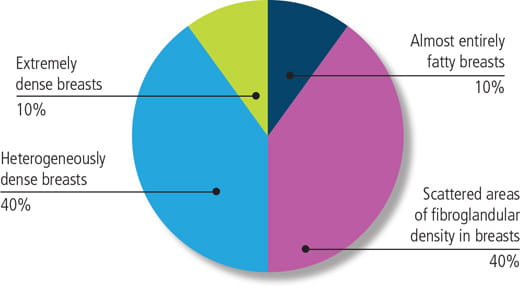

Radiologists classify breast density using a four-level density scale, as determined by a mammogram:

- Category A: Almost entirely fatty

- Category B: Scattered areas of fibroglandular density

- Category C: Heterogeneously dense

- Category D: Extremely dense

In the U.S., breast density is distributed as follows:

- 10 percent of women have almost entirely fatty breasts

- 10 percent have extremely dense breasts

- 80 percent are classified into one of the two middle categories